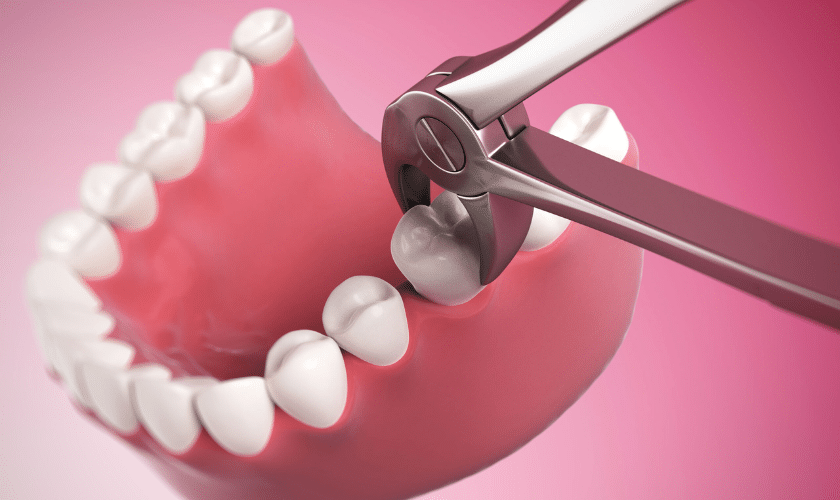

How Will My Wisdom Tooth Be Taken Out?

- Your dentist will perform a thorough clinical examination to determine whether surgical removal is necessary.

- An x-ray will be taken to check the position of the wisdom tooth.

- Surgery is usually performed under local anaesthesia. Intravenous sedation by a qualified anaesthetist can be arranged if required.

- After removal, the area will be stitched, and antibiotics and painkillers will be prescribed.